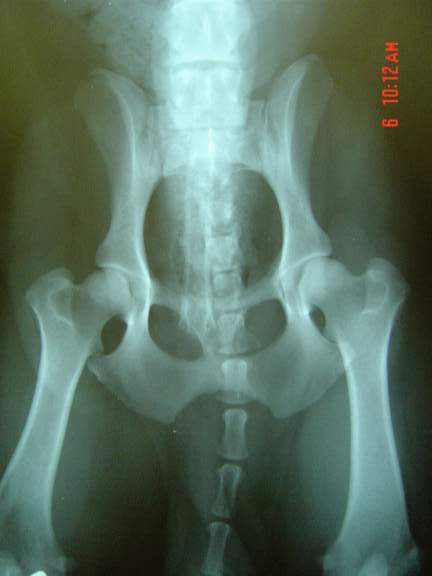

OFA Hips Good # PBG-444G111M-PI

Hip x-rays 2002

Harpad hip x-rays